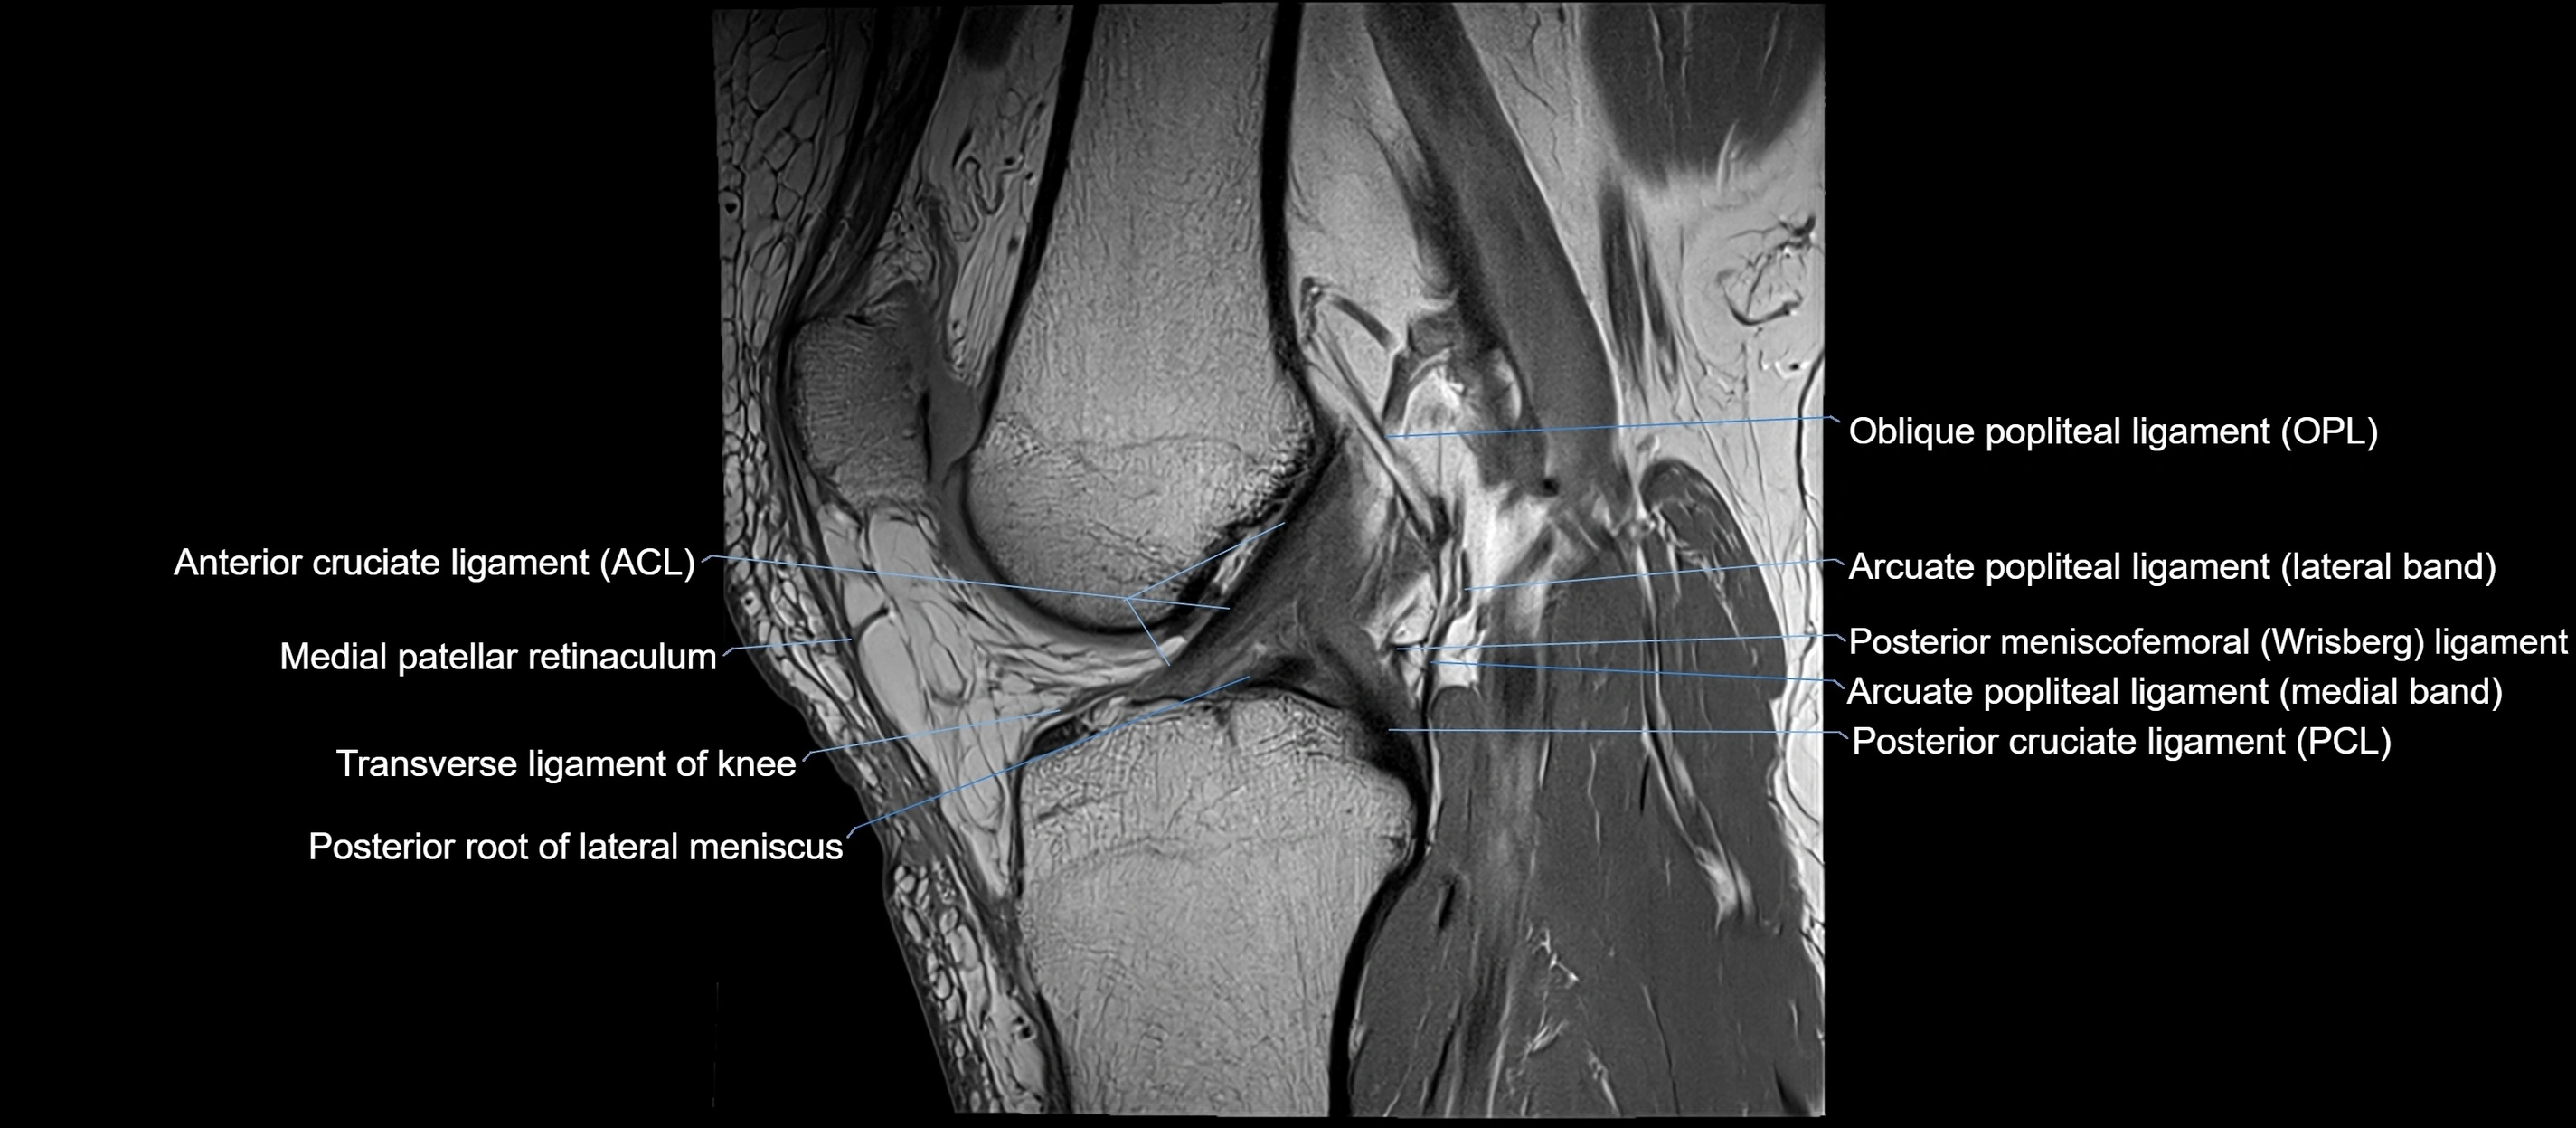

MRI images

image